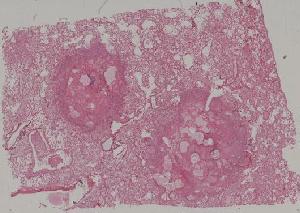

41.肺机会性感染